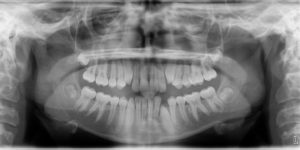

A 13-year-old female presents with a chief complaint that “My teeth aren’t in.”